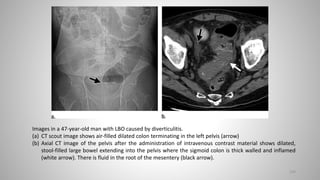

Images in a 47-year-old man with LBO caused by diverticulitis.

(a) CT scout image shows air-filled dilated colon terminating in the left pelvis (arrow)

(b) Axial CT image of the pelvis after the administration of intravenous contrast material shows dilated,

stool-filled large bowel extending into the pelvis where the sigmoid colon is thick walled and inflamed

(white arrow). There is fluid in the root of the mesentery (black arrow).